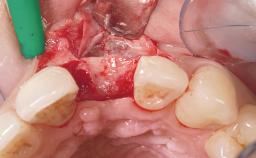

A 42-year-old female patient was referred to our clinic at the School of Dentistry of the University of São Paulo in November 2004, presenting a deficient restoration in the upper left central incisor. The clinical examination revealed no gingival retraction or any signs of gingival inflammation and, therefore, previous periodontal treatment was not considered. The patient presented a high lip line at full smile and a thin tissue biotype. This combination characterized a high-risk situation from an anatomic point of view, which required careful preoperative planning and cautious surgical execution.

Placement Protocol Immediate implant placement

Tooth Site Maxillary incisor or canine

Socket Morphology Single-root socket

Socket Integrity Sufficient, with intact bone walls